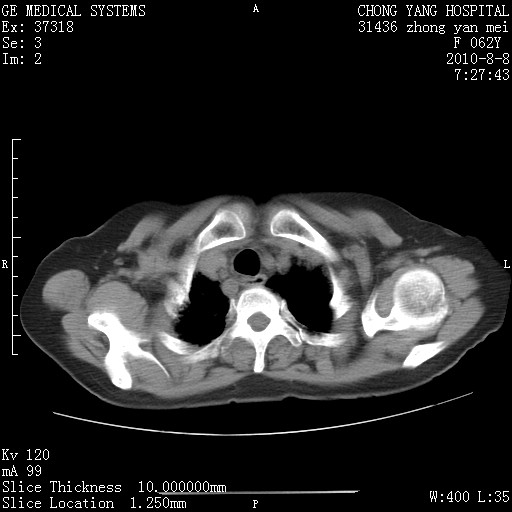

标题: CT28269:F62Y咳嗽胸痛数月。 [打印本页]

标题: CT28269:F62Y咳嗽胸痛数月。

另见右乳腺似有小钙化灶,建议进一步检查。

1.肺间质纤维化.

2.纵隔淋巴结肿大。

3.迷走右锁骨下动脉。